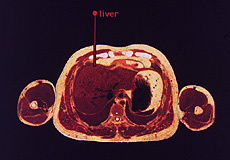

Installation image Items 1-2,000 collapses western medicine's fracturization of the body with industrial itemization techniques into the ultimate rationalization apparatus. A human body is half submerged in a block of wax, in a manner reminiscent of how biological specimens are fixed in a "microtome" (a machine which cuts these wax embedded specimens into slices often as thinly as 1 millimeter.) A sheet of glass rests several inches above the figure in a manner analogous to that of a cover slide used atop the cross sectional slices in microscopy. This glass is affixed with barcodes, running transversely across the glass, which correspond to internal organ locations of the figure underneath.

Participants interact with the work as anatomy students would a cadaver: They use a stainless steel barcode scanner much like a scalpel, slicing horizontally across the figure to reveal the hidden target organ. The more familiar use of barcodes and scanning procedures however are not lost, and this surgical role blurs with that of cashier, commodifying and extracting value through the denial of the body as whole (rather a rational composite of itemized parts.) Each targeted anatomical region has an axial, transverse and saggital center, so that once the program accesses the correct axial slice, an arrow points to the correct x and y location within this Cartesian corpus. Every third scan the participant makes accesses a jarred recollection from my own experiences as a student in the anatomy morgue. These recollections are somewhat poetic and primarily address the phenomena of de-humanization of the corpse as it is de-constructed and subsequently re-configured through dissection. These musings attempt to de-construct the rationalization processes of western bio-medical practices and to discover a point of empathy with the subject.

Screen grab The sliced human data-set used for Items 1 - 2,000 is exported from the National Institute of Health's Visible Human Project. CD-ROM. This was a multi-million dollar endeavor, in which a death-row inmate was given lethal injection, his internal cavities filled with latex, embedded in a wax-like gelatin, and sliced into 2,000 thin slices which were photographed and digitized. Certainly Foucault would have found the Visible Human project fascinating as the disciplined body of the prisoner is subjected to the ultimate surveillant process (minute dissection) and his body, essentially "drawn and quartered" in the ultimate spectacular punishment.1